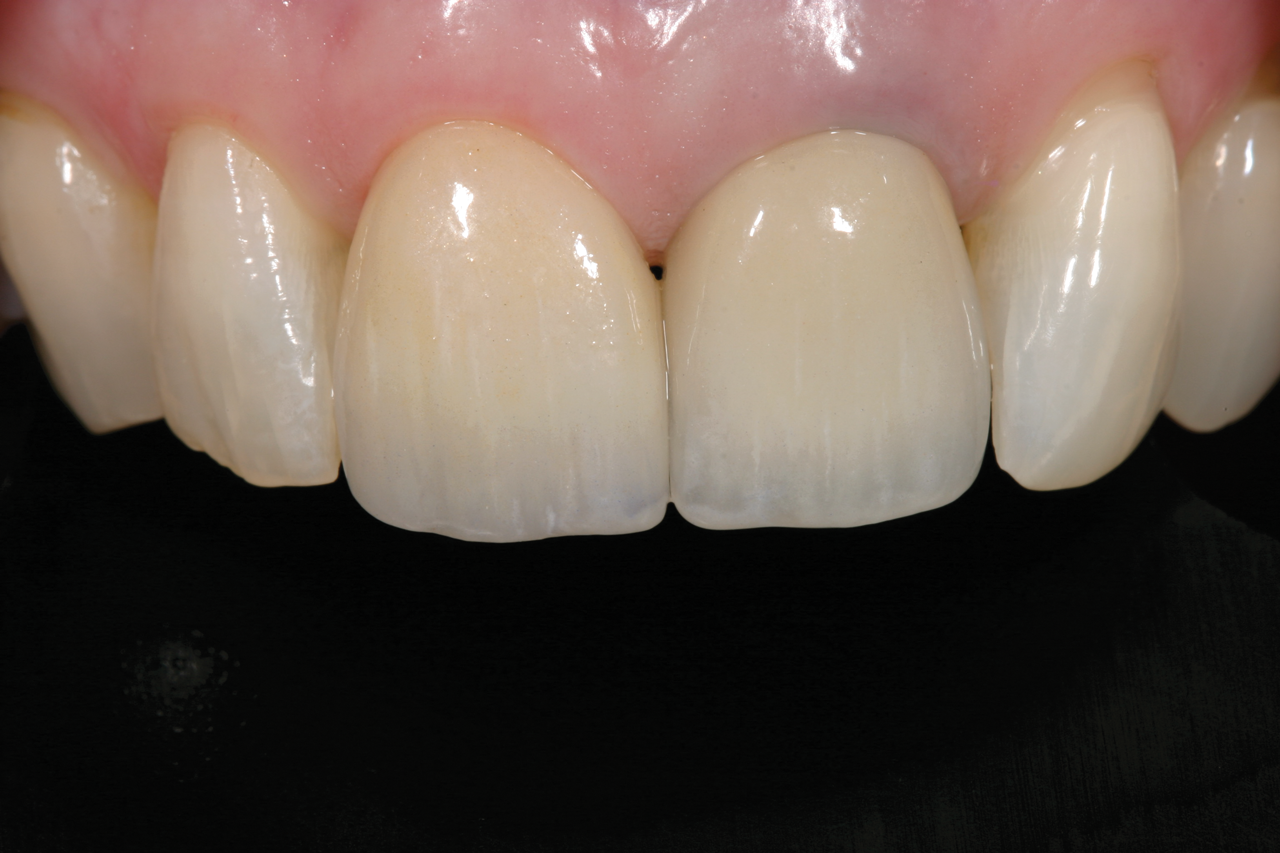

Fig 10. A 24-year follow-up radiograph of an endodontically treated tooth, with a cast post-and-core and adequate tooth structure remaining. The patient had a low smile line and thick phenotype.

Figure 10

Fig 11. Restoration at 24-year follow-up.

Figure 11

Coronal seal and maintaining 5 mm of gutta percha in the apical portion of the canal have also been shown to be critical, along with good coronal seal of the final restoration.4,5,11,23 Properly restored endodontically treated teeth can last many years when appropriately treatment-planned. Figure 10 and Figure 11 demonstrate a case in which tooth No. 8 was restored with a cast post-and-core and a properly fitted crown. The images show a 24-year follow-up on the tooth.